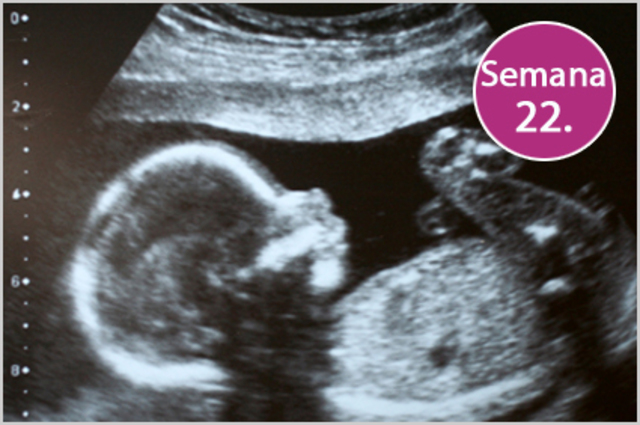

• Semana 22

Semana 22

-Se han descrito respuestas de parpadeo y susto.